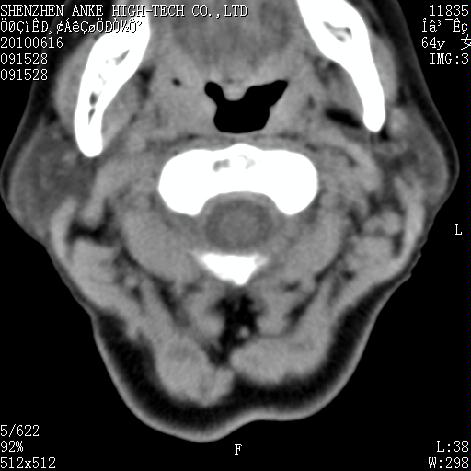

标题: CT27132:患者女,64岁,颈部及全身多处包块,现觉吞咽困难4 [打印本页]

标题: CT27132:患者女,64岁,颈部及全身多处包块,现觉吞咽困难4

右侧甲状腺占位,肿瘤可能性大,癌

右侧甲状腺癌伴右颌下腺淋巴结转移

右侧甲状腺癌伴淋巴结转移

右侧甲状腺癌伴淋巴结转移可能性大

右侧甲状腺癌伴淋巴结转移可能性大。

右侧甲状腺癌伴右颌下腺淋巴结转移!建议增强!